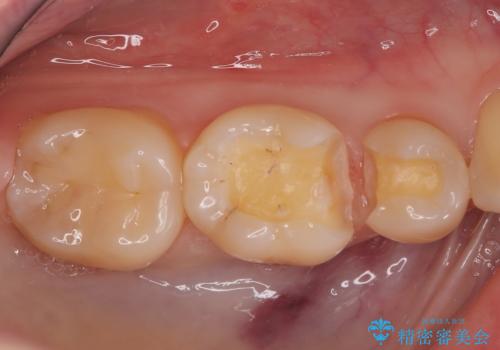

- 「銀歯を白しくしたい」を主訴に来院された患者さんです。

銀歯を外し、虫歯を除去した後にハイブリッドインレーで治療を行いました。